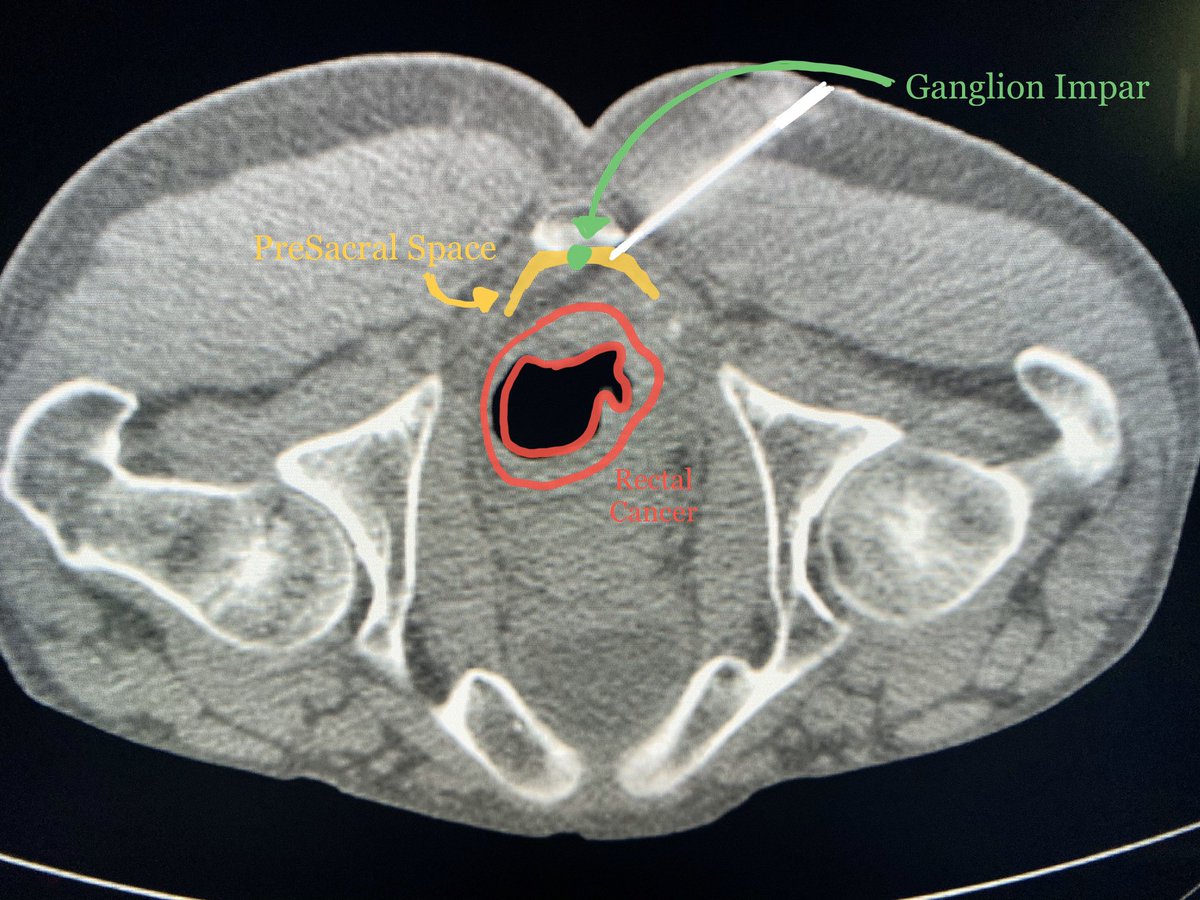

Ganglion Impar (GI) Block! GI is the end of the sympathetic chain, located within the extra peritoneal pre-sacral space at the level of the sacrococcygeal junction. Blocked usually with alcohol to treat coccydinia, vulvodynia and perianal pain.

#MSKRad#RadRes#educacionpic.twitter.com/3cTehwBGBa